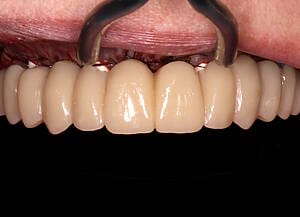

All data were transferred into digital treatment planning software, allowing virtual placement of implants and collaboration with the dental laboratory before surgery. This enabled careful evaluation of long-term outcomes and ensured the design of provisional and final prosthetics could be completed with precision. Following these discussions, the decision was made to proceed with the Fixed-Teeth-in-a-Day approach using the All-on-4 technique.

Surgical phase

The moment Natalie saw her new smile, the emotion was undeniable. What had once been a source of discomfort, anxiety, and embarrassment had been completely transformed. Her new teeth restored full function and aesthetics, giving her back the ability to eat, speak, and smile without hesitation.